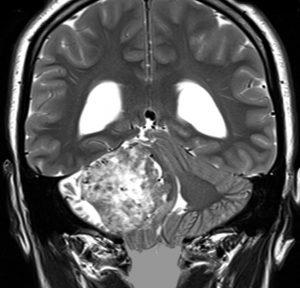

これは若い女性のもので,出産したすぐ後で発見されました。仕事もしていて知能も高い女性で,ひどい症状があって見逃されたものではありません。この時点でも普通に歩けますし,かるい頭痛とふらつきと右難聴くらいのものです。水頭症もあり,なんとか顔面神経を残して摘出できました。ここまでほっておくと命が危なくなるので,これで良いという意味ではありませんが,この大きさに近い聴神経腫瘍があっても妊娠出産もできるということです。もっと小さな聴神経腫瘍は慌てないでゆっくり考える。

MIB-1 5%と増大速度が速いタイプでした。